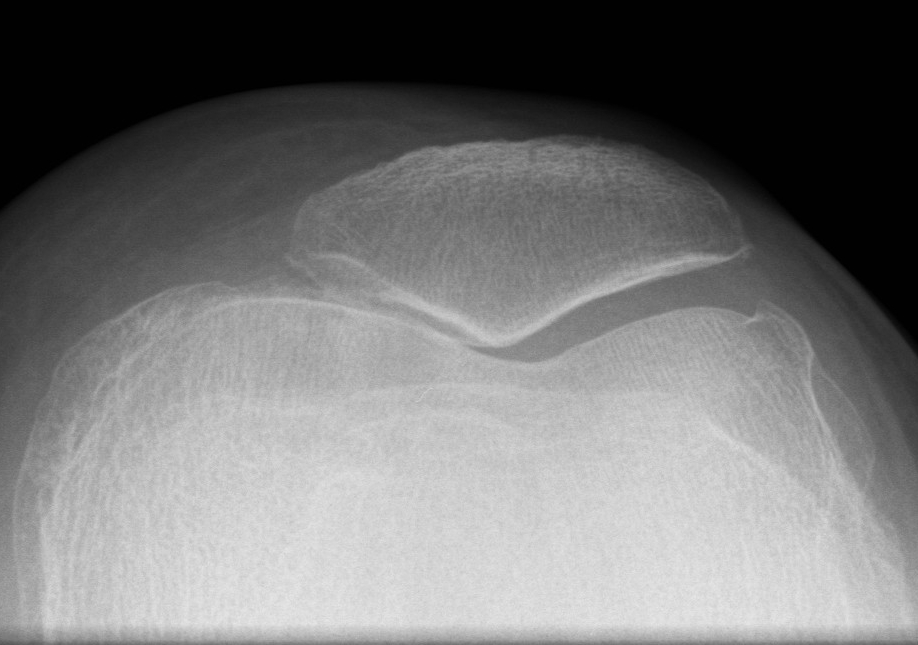

X-ray

Narrowing / osteophytes / sclerosis

Tilt / subluxation

Tilt Subluxation / osteophytes